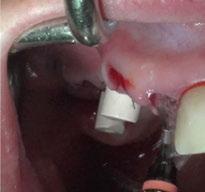

y lo que se pudo preservar del hueso malar. Se añadió una malla sinterizada infraorbitaria para dar volumen a la mejilla y se planificaron dos brazos de conexión que emergieran en las posiciones 24 y 26 de forma subgingival (Figuras 8 y 9). La superficie interna que apoyaba en el hueso era de titanio microrrugoso, y la superficie externa y conectores de titanio pulido y hexágono externo universal (Figuras 10 y 11). La cirugía se hizo bajo anestesia general en infiltración con anestesia local (4% articaína, 1:100.00 epinefrina), levantando el

colgajo cutáneo de la mejilla por vía intraoral, preservando el colgajo temporal para no comunicar con el remanente de la cavidad naso maxilar (Figura 12). Se emplearon 10 tornillos de osteosíntesis de 1,9 mm y la estabilidad primaria obtenida fue excelente (Figura 13)

4 meses después de la cirugía la encía estaba completamente cicatrizada y las conexiones de los implantes tipo hexágono externo universal quedaron a nivel yuxtamucoso. En este caso no se requirió el empleo de pilares transepiteliales y las impresiones fueron tomadas

directamente a cabeza de implante para realizar una prótesis dentoalveolar de cerámica de 3 piezas, que equilibraran la oclusión y dieran soporte al labio y la mejilla (Figuras 14-17)